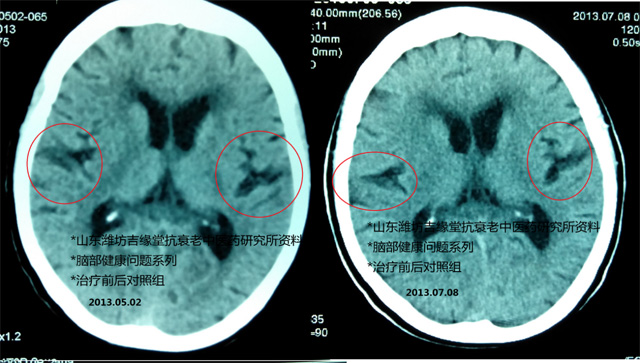

庄XX 治疗56天前后CT影像对比:

庄XX,2013年5月2日初诊,经治疗56天后,于2013年7月8日再做“CT”检查显示脑萎缩有明显改善情况,临床症状全部消失,治疗结果为治愈。